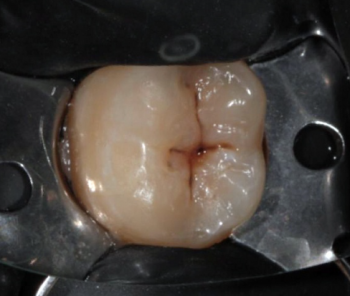

14 работ в портфолио